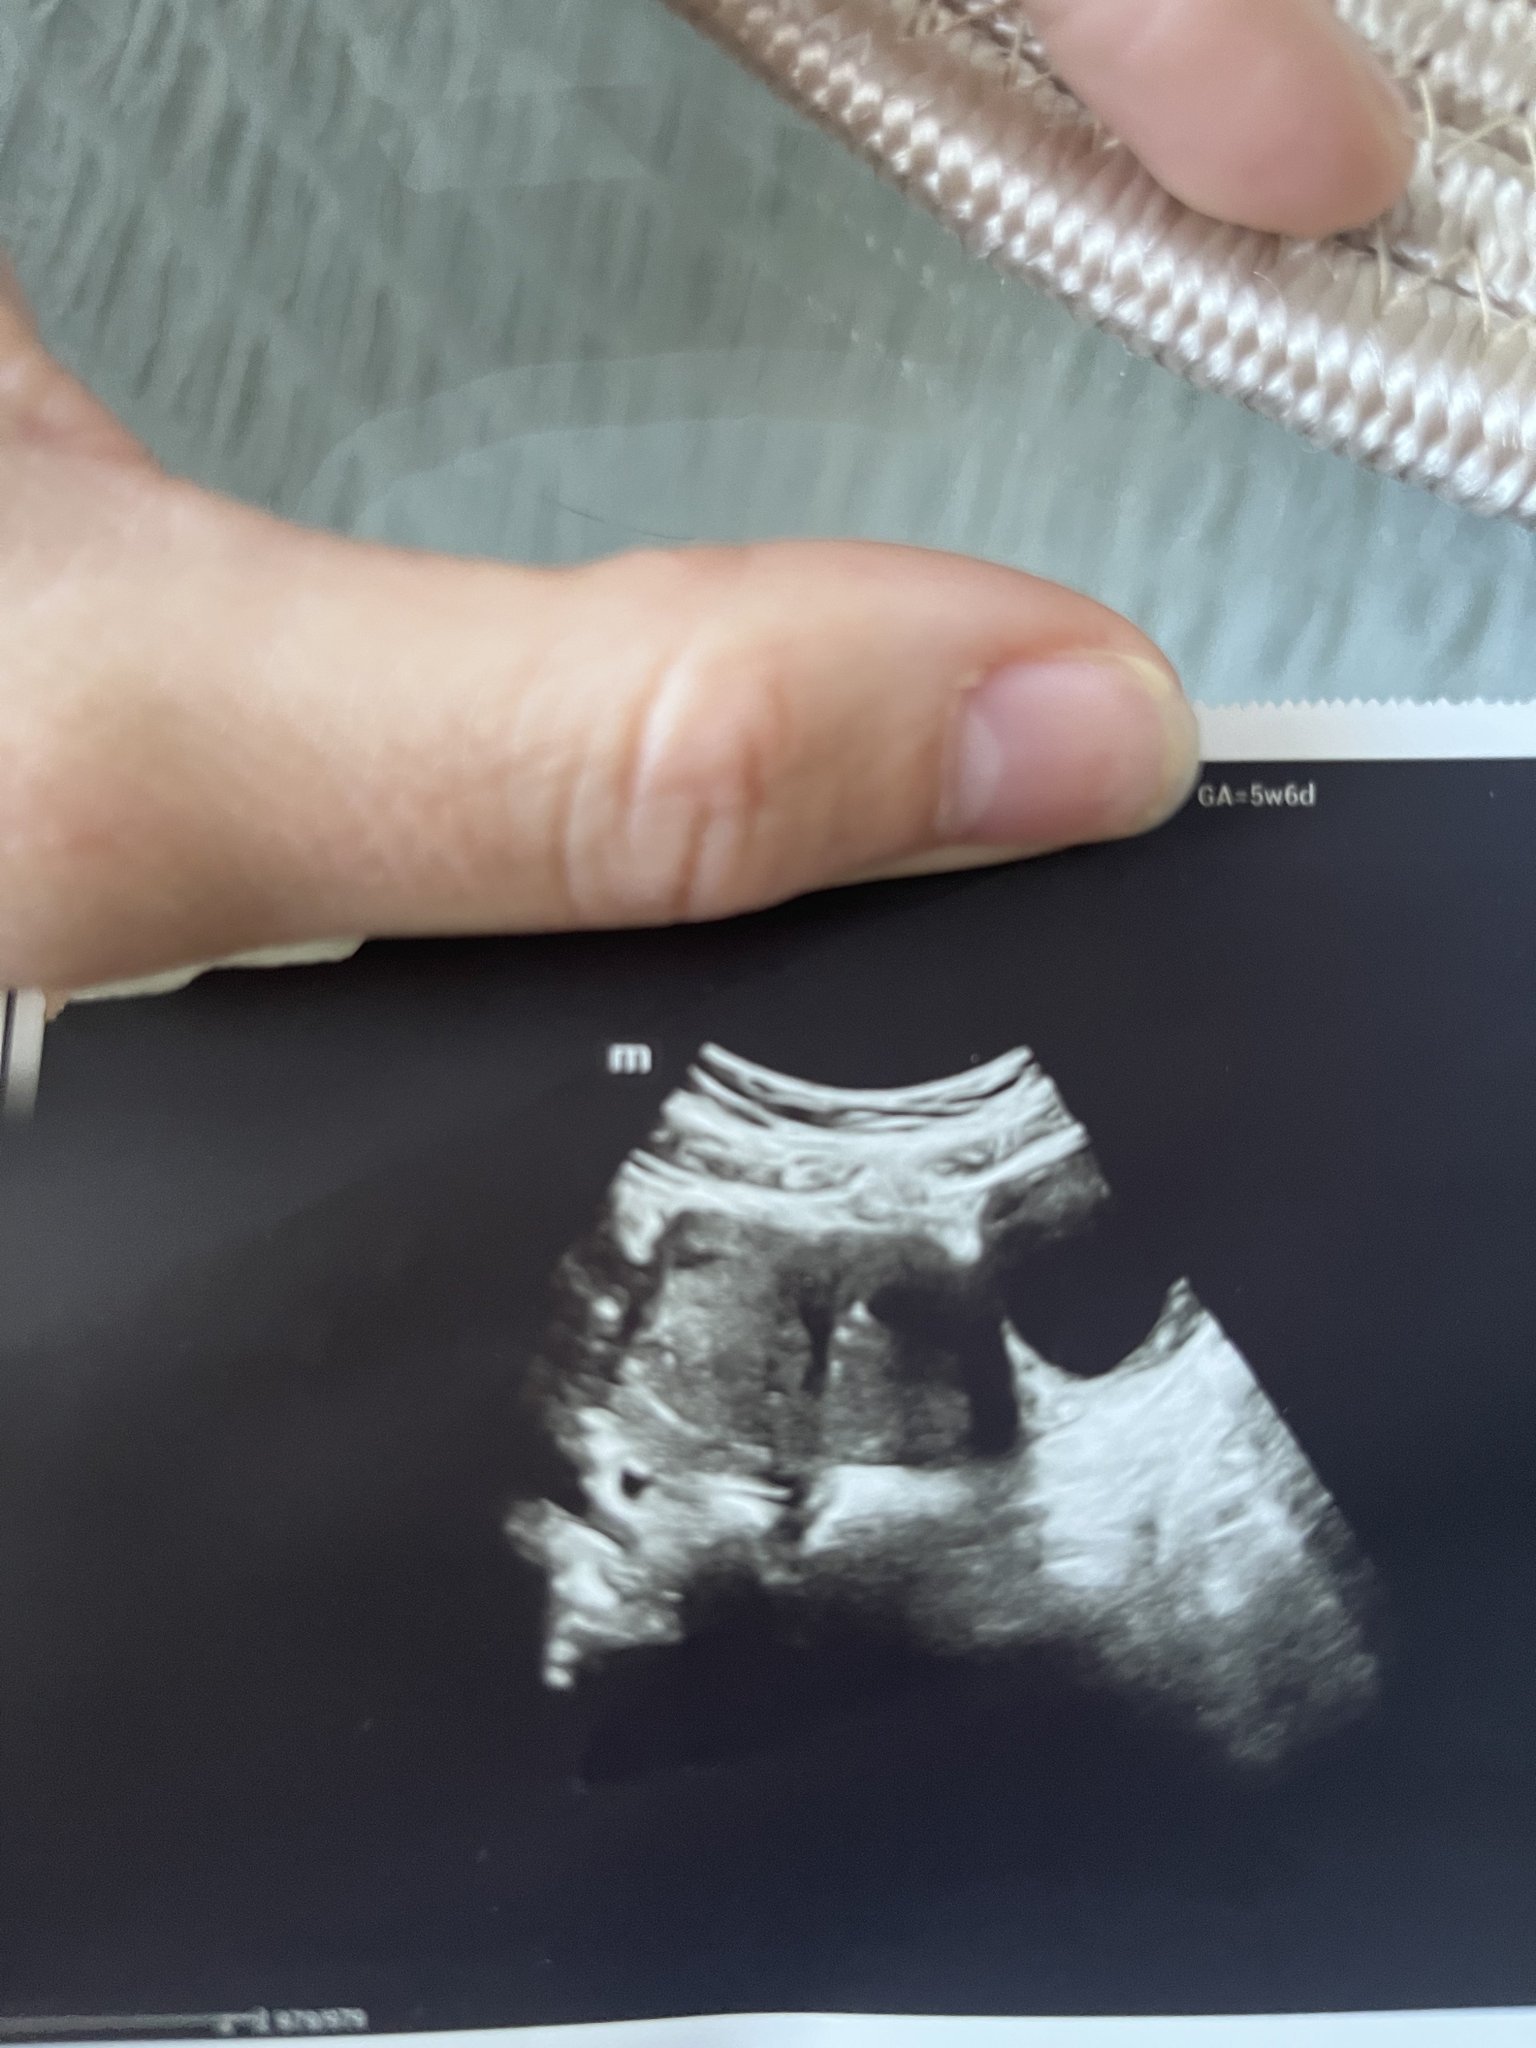

Първия ден на последната ми менструвация беше на 19.09.2023г. 4 положителни теста за бременност. Вччера беше първият ми преглед. Прикачам снимките от него. Видя се плоден сак с размер 18мм, ембрион не. Аз съм с две матки и плодния сак е в лявата матка. В левия яйчник имам и 40мм киста Sad . Притеснено ми е защо при тази големина на плодния сак не се видя ембрион. Преди 8 месеца претърпях куха беменност и се притеснявам изключително много да не се повтори. Чак след месец ще ми бъде следващия преглед, а до тогава ще се побъркам. Моля, ако някой може да помогне със съвет или е бил в подобна ситуация, да пише. Благодаря! Simple Smile

Може да се дължи на късна овулация. Но по принцип след 6г.с. може да се визуализира нещо (зависи и от техниката), Вие сте в 5+6 г.с. според снимката. Ако имате възможност отидете точно след седмица на преглед. Би трябвало всичко да е наред, стискам палци!